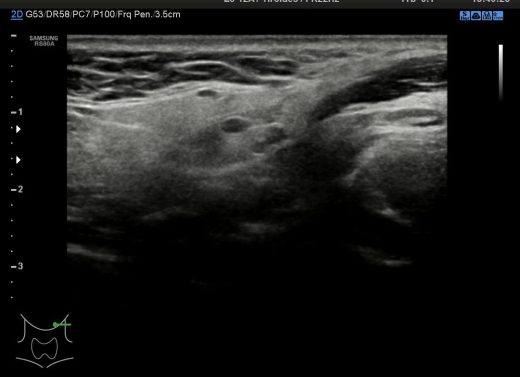

11. Región 4 Conducto del Tirogloso

12. Región 5

13. Región 6

14. Región 7

15. Región 8

Cada región del cuello tiene que tener una foto en el estudio y que puedes ver a continuación, el objeto de esta división es la búsqueda de ganglios locorregionales, así como otros hallazgos extratiroideos que pudieran ser de interés, calcificaciones carotídeas, Tiroides ectópico, incluso las glándulas submaxilares (espacio 1 y 6 pegados al 4) y parótidas (espacio 1 y 6, debajo del pabellón auditivo u oreja).

Con esta división nos garantizamos que repasamos la parte lateral del cuello (1,2,3,6,7,8) y la parte central – superior al Tiroides (4) donde encontramos el Conducto del Tirogloso. También el espacio número 5 o escotadura supraesternal donde pueden ocultarse ganglios o restos del Timo.

En condiciones normales no tenemos que encontrarnos hallazgos patológicos, pero es habitual ver ganglios que no deben sobrepasar el centímetro de diámetro en eje corto para ser considerados normales, todos los hallazgos no normales deben ser registrados para posterior evaluación del Radiólogo/a.